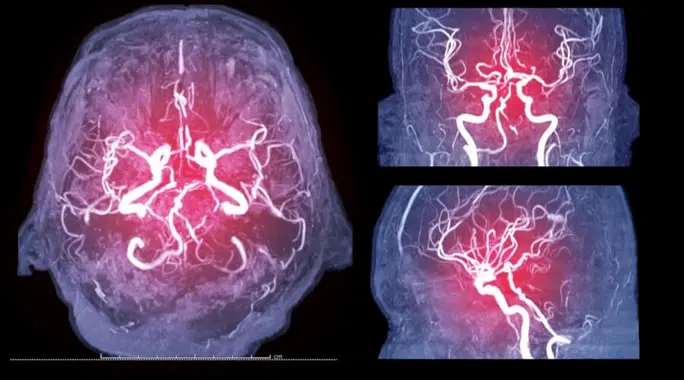

تُعرف قسطرة الدماغ، أو التصوير الوعائي الدماغي، بأنها إجراء طبي دقيق يهدف إلى فحص الأوعية الدموية داخل الدماغ. يستخدم الأطباء هذه التقنية لتحديد أي مشكلات أو تشوهات في تدفق الدم أو بنية الأوعية.

تساعد هذه الصور الأطباء على رؤية تفاصيل دقيقة للأوعية الدموية، مما يمكنهم من تشخيص مجموعة واسعة من الحالات بدقة عالية، وفي بعض الأحيان، يمكن استخدام القسطرة للعلاج أيضاً.

يُجري الأطباء قسطرة الدماغ عندما تشير الفحوصات الأولية، مثل التصوير بالرنين المغناطيسي أو الأشعة المقطعية، إلى وجود مشكلة محتملة في الأوعية الدموية الدماغية. توفر صور القسطرة الدماغية دقة أكبر وتفاصيل أعمق، مما يجعلها حاسمة في التشخيص وتخطيط العلاج.

- التقاط الصور: تُؤخذ سلسلة من صور الأشعة السينية التي تظهر الشرايين وتدفق الدم في الأوعية والشعيرات الدموية، مما يسمح للطبيب بتقييم حالتها.